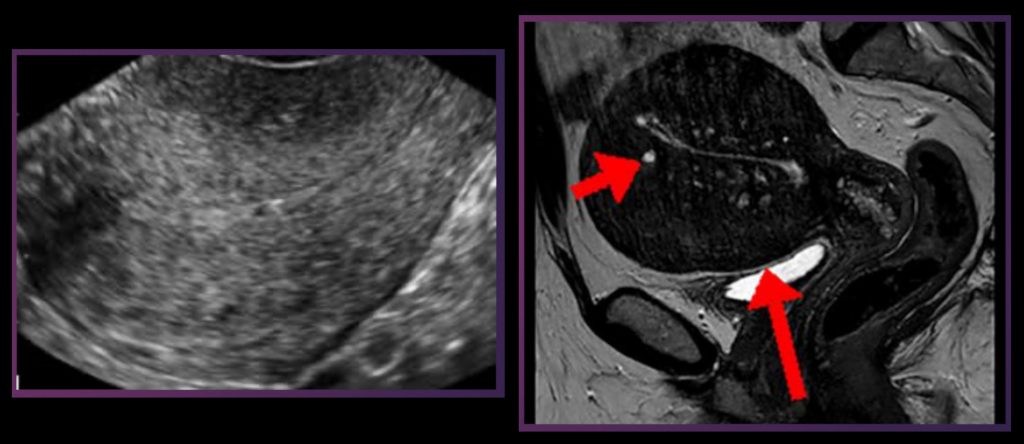

The disease is suspected in women with painful periods and heavy vaginal bleeding in the absence of other explanations for the symptoms. Your doctor may order imaging such as ultrasound or MRI to support the diagnosis and rule out other causes.